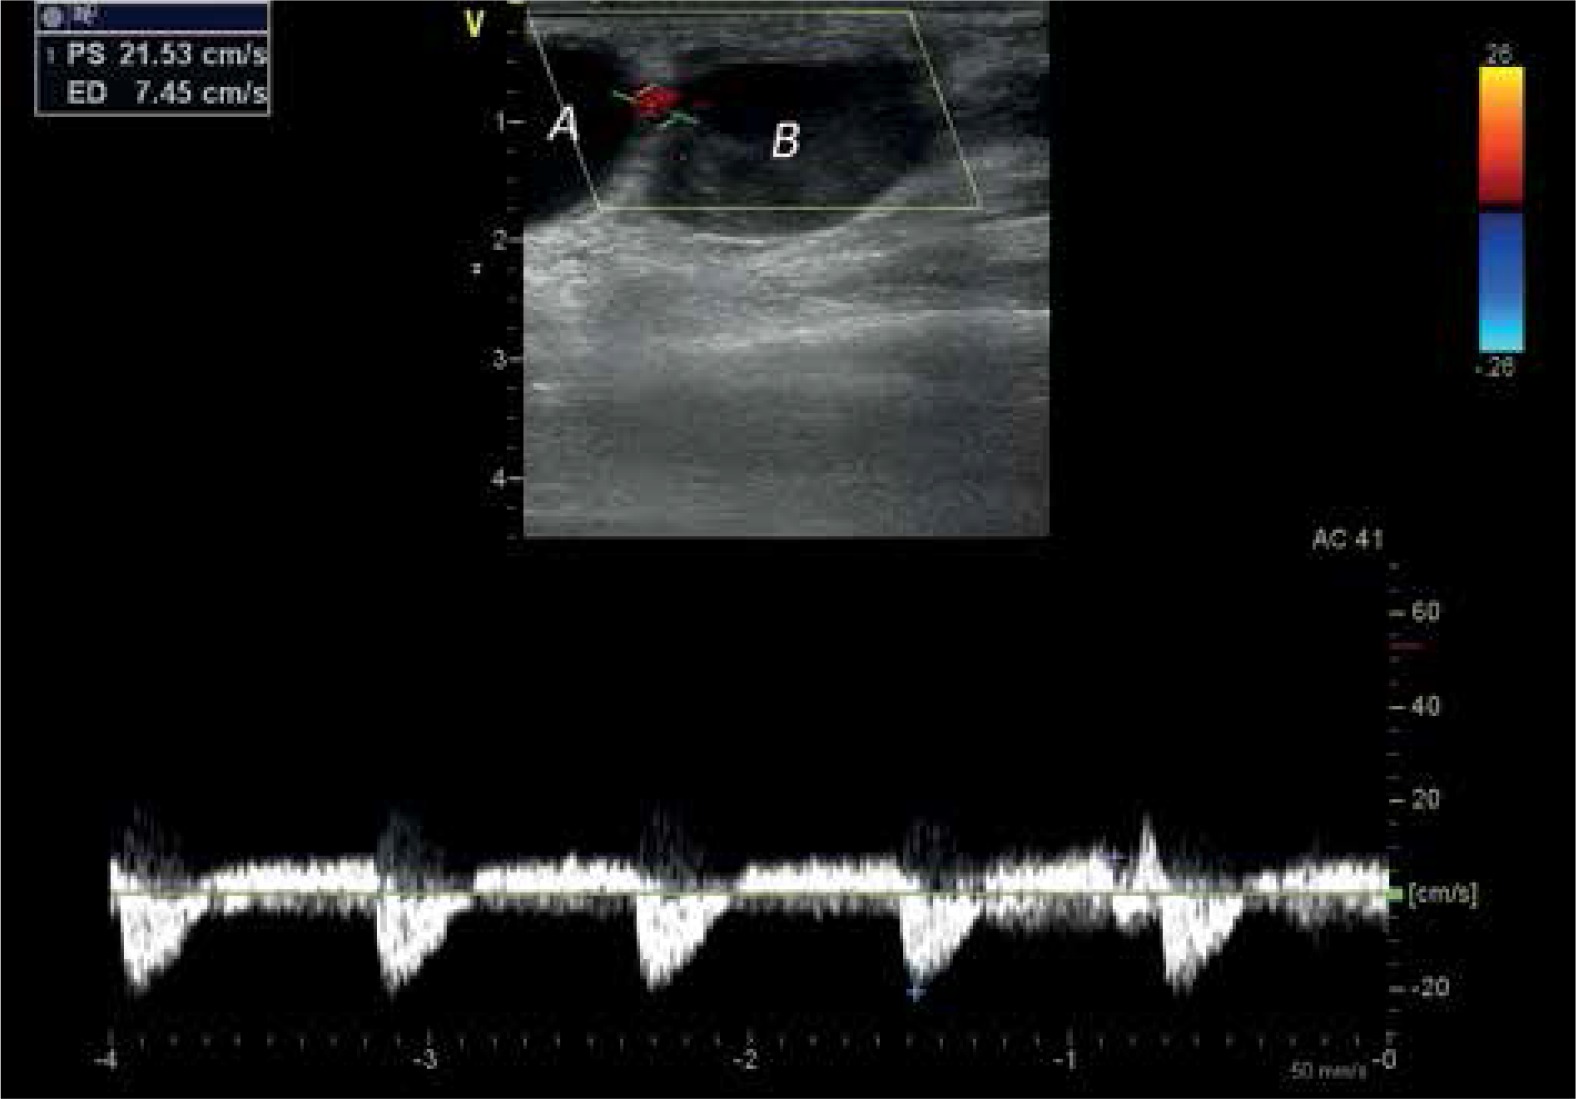

Figure 5

Effect of thrombin injection resulting in complete flow stop by clot filling first of the chambers

A – first chamber, B – second chamber, RA – radial artery.